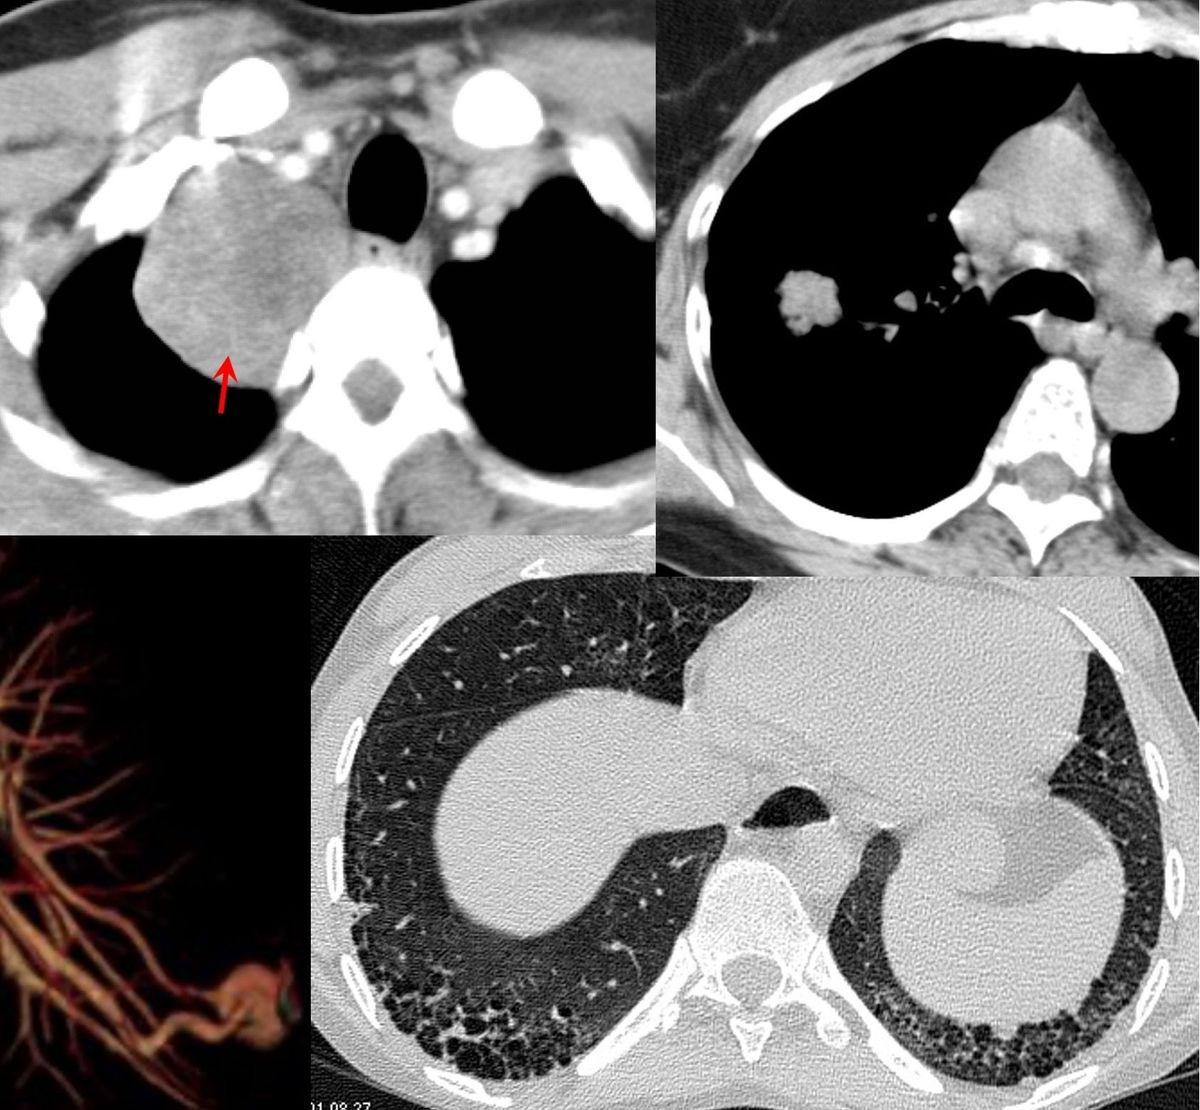

37-years old with gradually progressive dyspnea.

Upper lobe reticular opacities with volume loss, extending below tracheal bifurcation, small left pneumothorax.

CT images show classic findings of pleuroparenchymal fibroelastosis (PPFE), with no other associated etiology, hence idiopathic - iPFFE.

The video describes all the additional findings that often go hand in hand as in

- Playthorax - flat chest - progression of platythorax associated with poorer prognosis

2l Anterior and downward rotation of the ribs - associated with poorer prognosis - Reduced upper lobe lung volumes